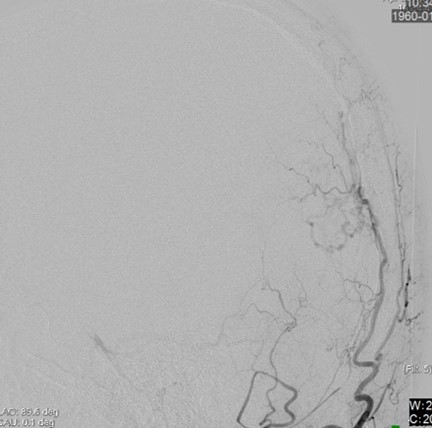

【DSA (左後頭動脈)】

後頭葉脳表に皮質静脈に直接灌流する動静脈瘻

• 側面

• 正面

診断:Cognard Type III 硬膜動静脈瘻による静脈性梗塞(静脈高血圧性脳症)